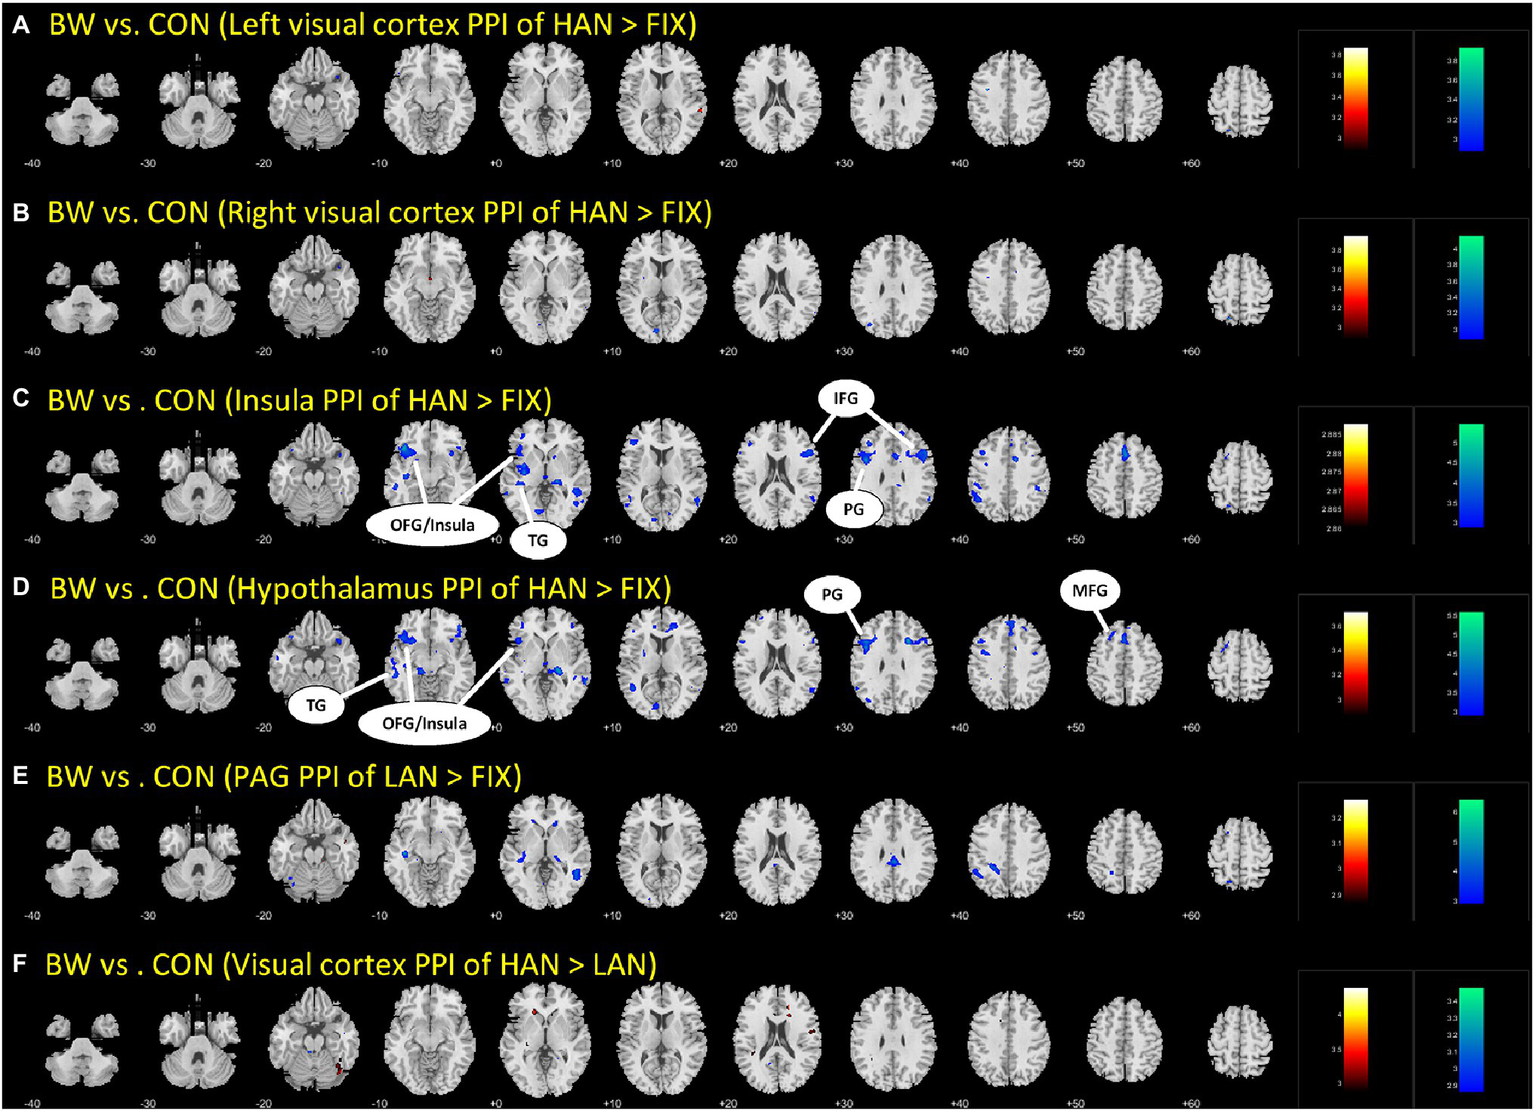

Brain regions showing differences between BWS and CON as in Table 3 were used as seed regions for PPI analysis. Patterns of significantly differing PPI between BWS and CON groups were observed at voxel p < 0.005 uncorrected and cluster-level p < 0.05. FWE corrected when the hypothalamus and insula were used as seed regions for the PPI. No difference was observed for other seeds. In both cases, the CON group showed significantly increased incidence of PPIs (Figure 3; Table 4). Notably, in the CON group, evidence of functional connectivity during HAN presentation was seen between the insula and the orbitofrontal, inferior frontal and superior temporal cortices, and the prefrontal gyrus. In addition, during HAN image presentation, the CON group also showed significantly increased PPI between the hypothalamus and the insula, superior temporal cortex, precentral gyrus, and middle frontal cortex.

Figure 3

The different parts (A-F) are simply the different brain regions and conditions tested in the PPI analysis. Differences in PPI between BWS and CON during HAN image presentation. OFG, Orbitofrontal gyrus; TG, temporal gyrus; IFG, inferior frontal gyrus; PG, Precentral gyrus; and MFG, Middle frontal gyrus.

We observed significant PPI interactions between multiple brain regions during HAN image presentation in CON that were not present in BWS. Notably, in CON, the insula showed significant PPIs to frontal and temporal cortical regions, which has been identified previously in healthy adults regulating during aversive image presentation (Veit et al., 2012). The lack of PPIs in response to the same stimuli in BWS may indicate a difference in regulation strategies utilized by participants in the two groups. Similarly, the hypothalamus also showed significant PPIs between the insula, frontal, and temporal cortices during HAN image presentation in CON compared with BWS. Engagement of PPIs in the hypothalamus during negative affective image presentation is a novel finding that has not been previously reported in other studies of affective image presentation and fMRI responses. However, activation of these areas during threat and negative affective image presentation is not unprecedented. Taken together, these findings show that while participants in the CON group display evidence of PPIs that are commonly associated with emotion regulation in response to threat, BWS participants did not. Similar observations have been shown in elite and non-elite military as well as extreme sports athletes, with less-experienced performers displaying higher levels of physiological reactivity to threatening or stressful situations (Clemente-Suárez et al., 2017; Tornero-Aguilera et al., 2017). Of note, however, there was no significant difference in years of experience surfing between the BWS and CON cohorts, indicating that although the two groups had an equivalent level of experience, the respective difference in threat associated with participation in the sport between the two groups may be driving the neurophysiological differences seen.